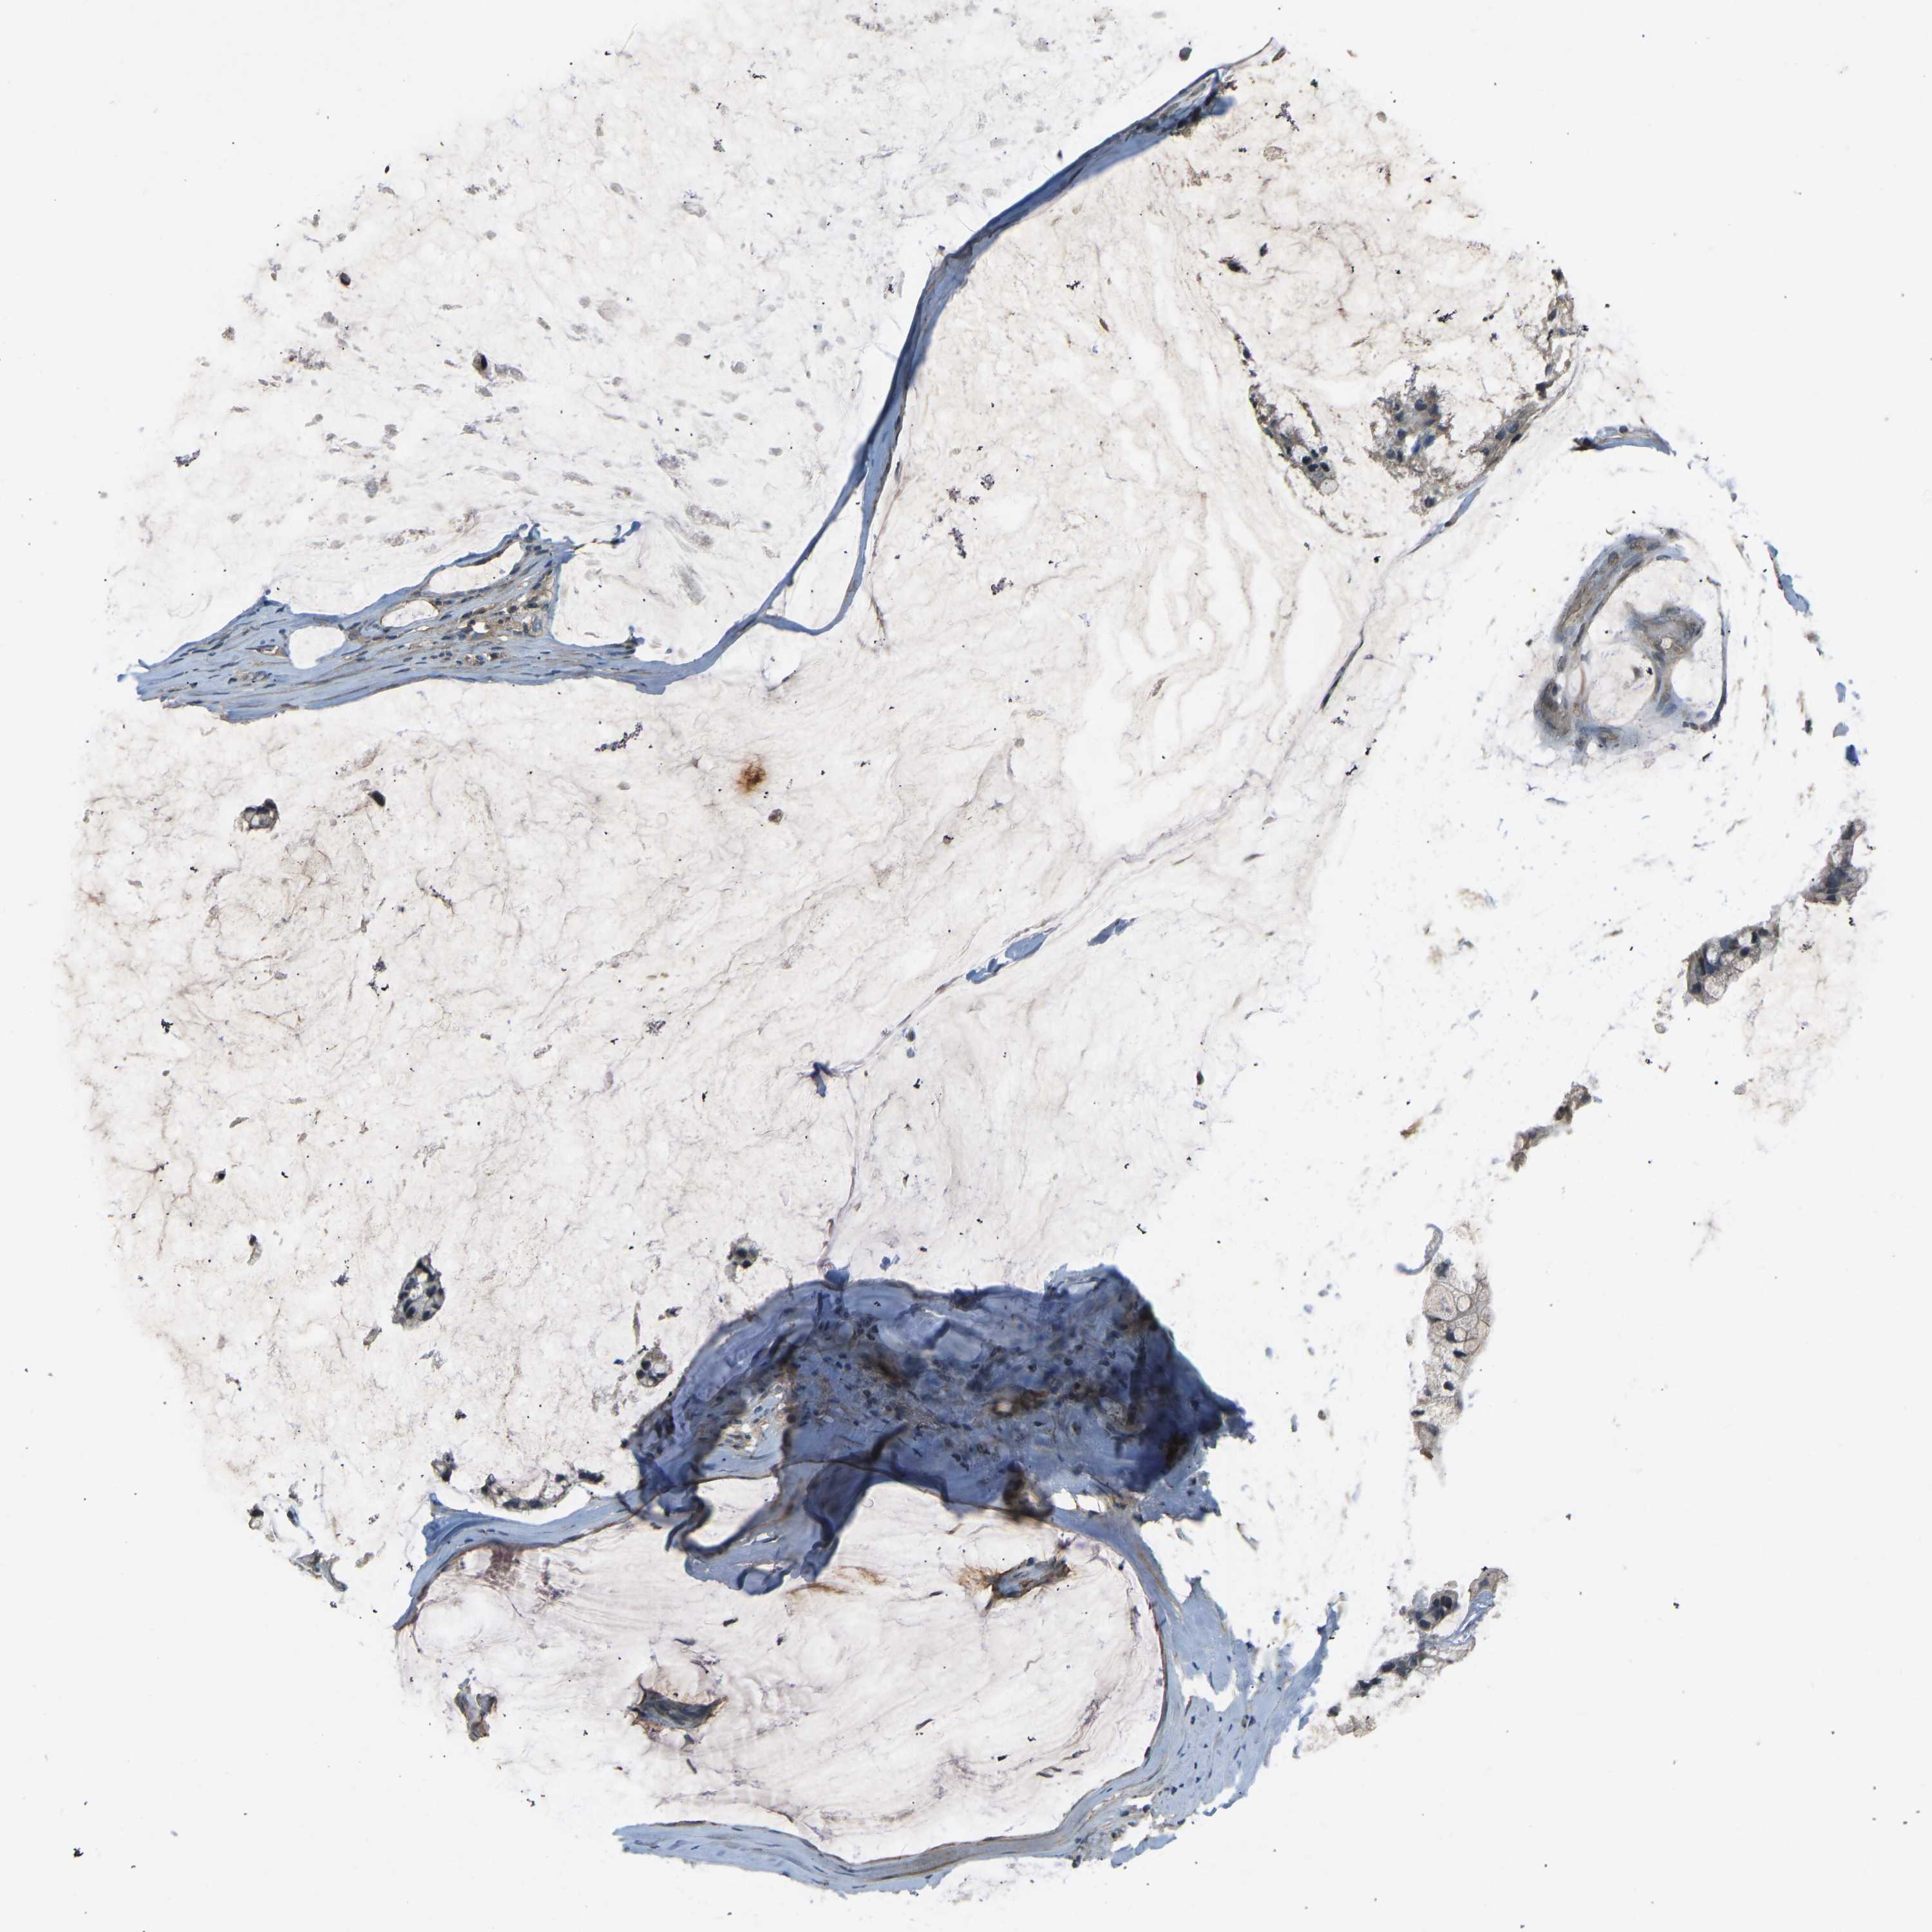

OVARIAN CANCER - Protein expressioni

A mouse-over function shows sample information and annotation data. Click on an image to view it in a full screen mode. Samples can be filtered based on level of antibody staining by selecting one or several of the following categories: high, medium, low and not detected. The assay and annotation is described here.

Note that samples used for immunohistochemistry by the Human Protein Atlas do not correspond to samples in the TCGA dataset.

Antibody stainingi

Antibody staining in the annotated cell types in the current human tissue is reported as not detected, low, medium, or high, based on conventional immunohistochemistry profiling in selected tissues. This score is based on the combination of the staining intensity and fraction of stained cells.

Each image is clickable and will lead to virtual microscopy that enables deeper exploration of all samples and also displays staining intensity scores, fraction scores and subcellular localization as well as patient and tissue information for each sample.

Antibody HPA001934

Antibody CAB018622

Cystadenocarcinoma, mucinous, NOS

Carcinoma, endometroid

Cystadenocarcinoma, serous, NOS

Carcinoma, NOS